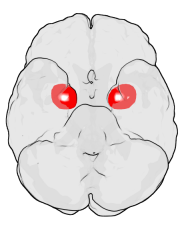

![]() تقسيمات لوزة المخ. | |

The regions described as amygdala nuclei encompass several structures of the cerebrum with distinct connectional and functional characteristics in humans and other animals.[4] Among these nuclei are the basolateral complex, the cortical nucleus, the medial nucleus, the central nucleus, and the intercalated cell clusters. The basolateral complex can be further subdivided into the lateral, the basal, and the accessory basal nuclei.[5][6][7]

Amygdala along with other subcortical regions, in glass brain.

Dorsal view of the amygdalae in an average human brain

Frontal view of the amygdalae in an average human brain